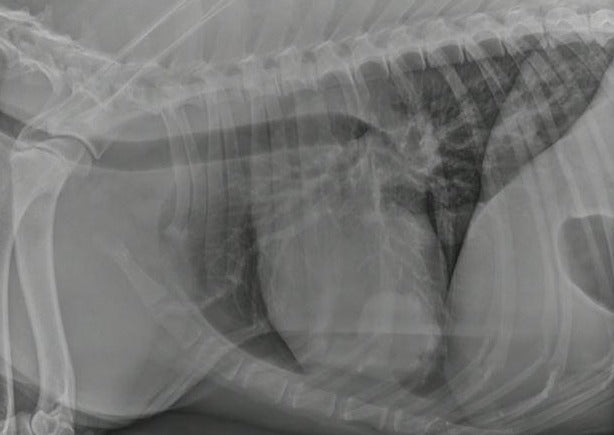

Is That Normal for an Old Dog (or Cat)? Geriatric Variants in Radiology

We never see 'normals' anymore. Hardly anyone takes radiographs of healthy animals. Especially when you start dealing with older animals, you might wonder what 'normal' looks like since you have nothing to compare your radiographs to. How do you figure out what 'normal' is and what is going on with your patients?